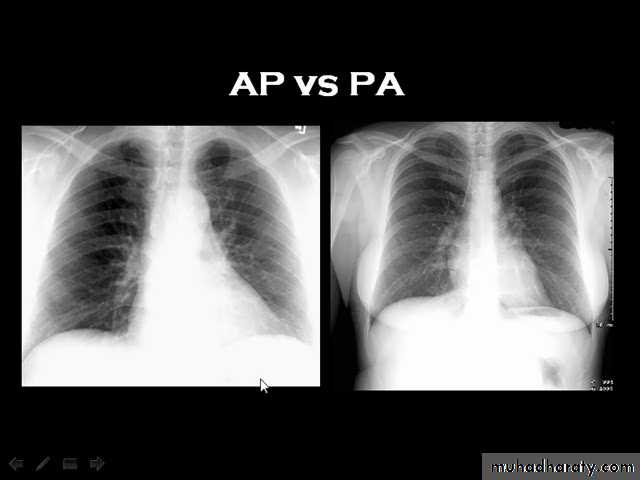

Techniques - Projection

P-A (relation of x-ray beam to patient)Supine view (AP)